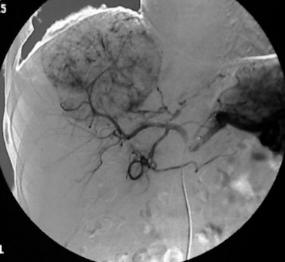

肝癌是最常见肿瘤之一

当然,医学上的命名相对复杂。医学术语的“癌”,它的定义明确指向到“起源于上皮组织的恶性肿瘤”。换句话说, 癌 其实只是通常所说癌症的一部分。也许是因为“癌”是最常见恶性肿瘤的缘故,大家也就默认将所有恶性肿瘤统称为癌症了。相对应的,医学上将起源于间叶组织的恶性肿瘤称为“肉瘤”;有少数恶性肿瘤则以加上“母”或“恶性”等来明确恶性肿瘤,如肾母细胞瘤、恶性畸胎瘤、恶性淋巴瘤等。